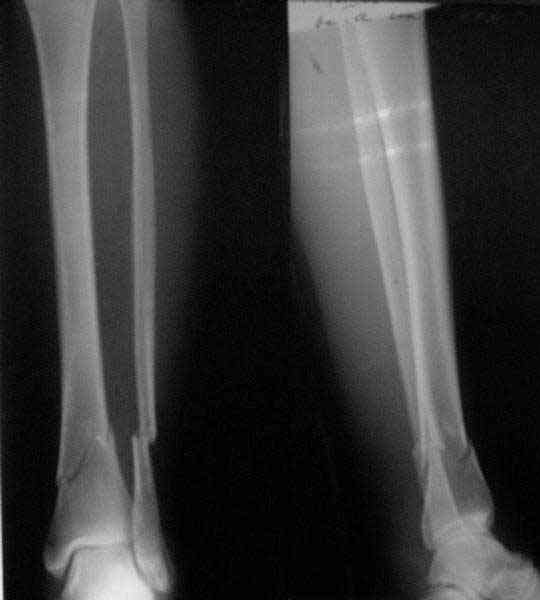

Проксимальный и дистальный переломы tibia

Направили к нам пациентку 35 лет с переломом дистального отдела костей голени.

У нас сделали снимок сзахватом обоих суставов - еще и проксимальный метафиз сломан. Чем бы у вас фиксировали такой перелом? Как его правильно закодировать по классификации АО?

Можно либо как два перелома - 41A+42B. А можно как один сегментарный 42С.

41.A2.1 for a proximal fracture

42.B1.3 for a distal fracture

Is very difficult take an exactly AO/OTA group for a good classification Probably the locked IM nail is a good option.